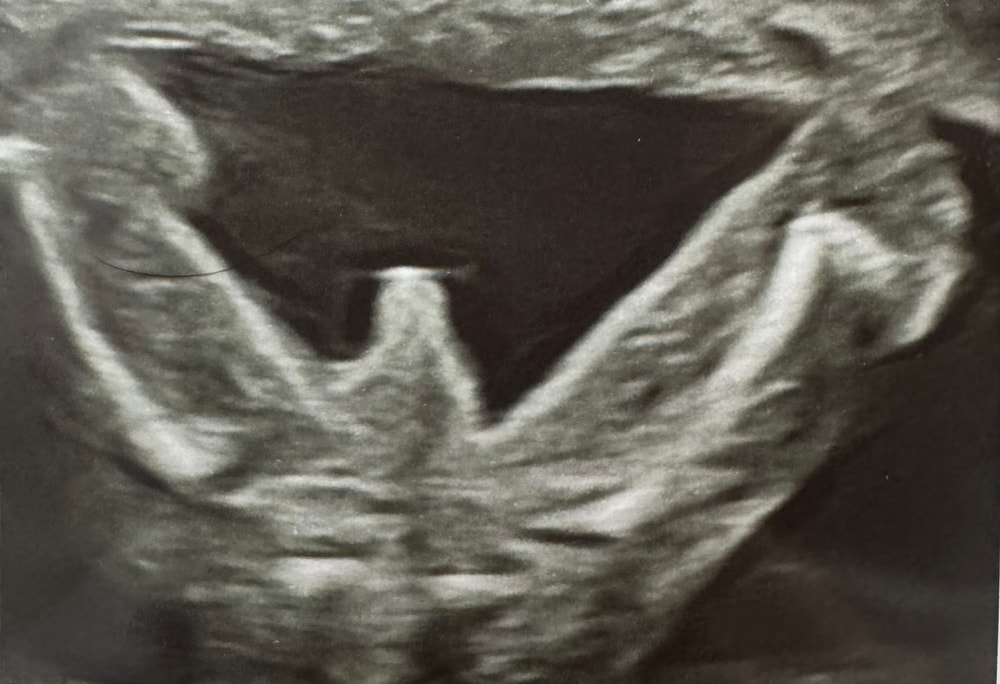

Долго не хотел раздвигать ножки, чтобы подтвердить пол. Но все же сдался!) ждём мальчика 100%, пруфы в комментариях (осторожно, легкая эротика 😂).